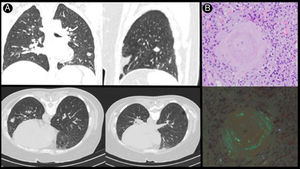

Mujer de 45 años con antecedente de linfoma no Hodgkin tipo mucosa-associated lymphoid tissue, con respuesta completa tras tratamiento. En la tomografía computarizada (TC) de control se objetivan lesiones nodulares múltiples de localización subpleural y quistes pulmonares (fig. 1A) con baja captación en la tomografía por emisión de positrones/tomografía computarizada (TC) (SUVmáx. 1,3). Como hallazgo casual en mamografía se objetiva nódulo mamario y lesión cutánea en miembro inferior que se biopsia con resultado diagnóstico de amiloidosis AL-kappa. Ante la sospecha de amiloidosis nodular pulmonar (ANP) se realiza biopsia con aguja gruesa guiada por TC que muestra material rojo Congo positivo (fig. 1B) y cadenas ligeras kappa intensamente positivas en el estudio inmunohistoquímico, estableciéndose el diagnóstico de amiloidosis sistémica AL-kappa.

La ANP es una enfermedad infrecuente que se caracteriza por la presencia de uno o más depósitos de tejido amiloide en el pulmón. La amiloidosis primaria es la más frecuente siendo la amiloidosis sistémica rara. Los pacientes suelen estar asintomáticos representando un hallazgo incidental en estudios de imagen donde se objetivan nódulos de 0,4-5cm bien definidos de distribución subpleural. Para su diagnóstico es preciso el análisis histológico en el que se objetiva material eosinófilo que tiñe con rojo Congo con una birrefringencia verde manzana1,2.